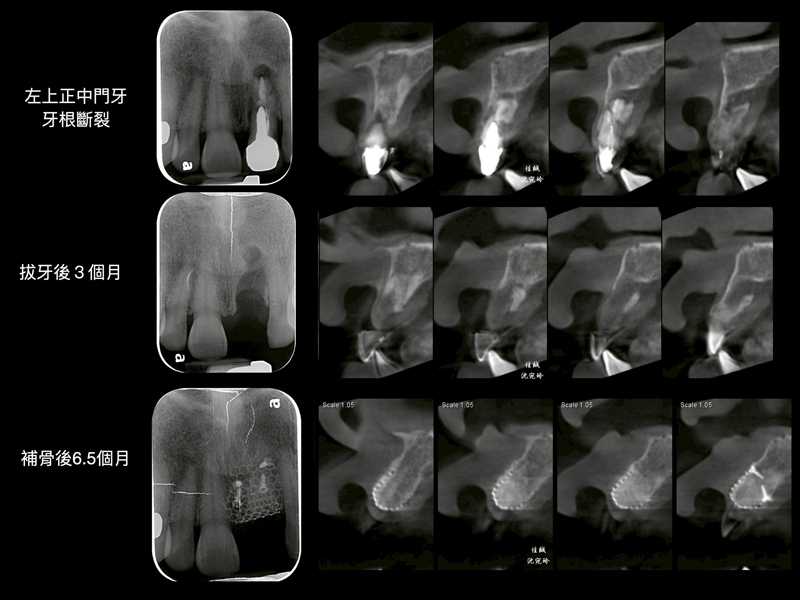

案例分享 首頁 案例分享 『植牙困難』案例分享 MORE 案例分享『矯正前之困難補骨』 MORE 案例分享『困難植牙』 MORE 案例分享『牙齒凌亂,不敢開懷大笑該怎麼辦?』 MORE 案例分享『斷裂器械移除』 MORE 案例分享『全口重建』 MORE 案例分享『活性牙髓治療(覆髓)- 蛀牙免根管治療的新選擇!』 MORE 案例分享『牙齒斷裂,利用水雷射補骨重建』 MORE 案例分享『上顎後牙區角質化上皮移植術(FGG)』 MORE 案例分享『第三代LITETOUCH水雷射舌繫帶切除』 MORE «1»